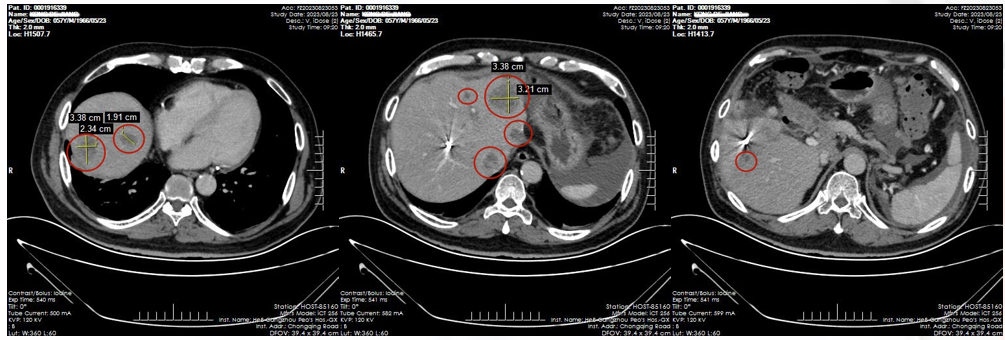

2023-08:复查显示肝内转移、腹膜及大网膜多发转移(图1)。

2024-03:6周期后复查评估,病灶持续缩小(图2),疗效评价确认为PR(部分缓解)。